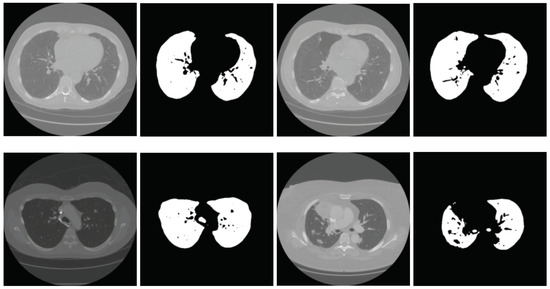

2.2.1. Segmentation in Lung Window

2.2.2. Segmentation in Mediastinal Window